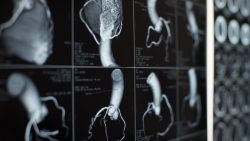

Before surgery, you may have to have an electrocardiogram (ECG or EKG), blood tests, urine tests, and a chest x-ray to give your surgeon the latest information about your health.

The procedure is performed with general anesthesia in a hybrid suite (which has both catheterization and surgical capabilities). A team of interventional cardiologists and imaging specialists, heart surgeons and cardiac anesthesiologists work together, using fluoroscopy and echocardiography to guide the valve to the site of implantation/replacement.